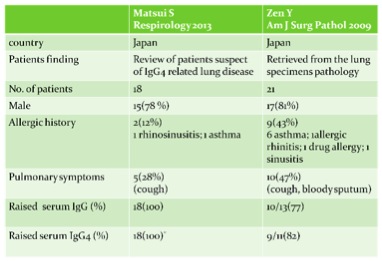

There is still no published consensus about the diagnostic criteria of igG4-related disease. Most studies are using diagnostic criteria by Umehara and colleagues in 2011: 1) clinically showing characteristic diffuse or localized swelling or masses in single or multiple organs, 2) hematological examination shows increased serum IgG4 concentration, 3) histopathologic examination showing a) marked lymphocyte and plasmacytic infiltration and fibrosis, and, b) infiltration of IgG4 + plasma cells: ratio of IgG4+/IgG+ cells more than 40% and more than 10 IgG4+ plasma cells per high power field. Patient can be diagnosed as definite (fulfill all 3 criteria), probable (fulfill the 1st and 3rd criteria), and possible (fulfill the 1st and 2nd criteria) IgG4-related disease (3). According to 2 series from Japan, the incidence of lung involvement of IgG4-related disease can range from 14 to 54% (4,5). There are two relatively large scale case series published by Matsui S in Respirology 2013 and Zen Y in Am J Surg Pathol 2009 to describe the clinical features of patients with IgG4-related lung disease. Both series showed male predominance around 80%. There were 12% and 43% of patients in respective series having allergic history like rhinosinusitis and asthma. Only 28% and 47% of patient in respective series having pulmonary symptoms and mostly complained cough. The radiological features of lung manifestation were described in Zen study, which can be nodular, bronchovascular interstitial, ground-glass opacity or pleural lesion. (table 2,3) The possible radiological findings of IgG4-related lung disease were also described in review article by Ryu in Eur Respi J 2012 (table 4) (6).